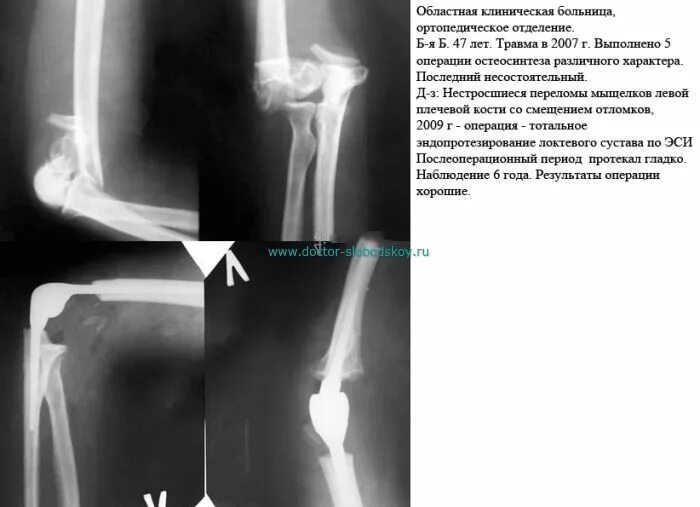

Перелом локтевой сустав мкб 10